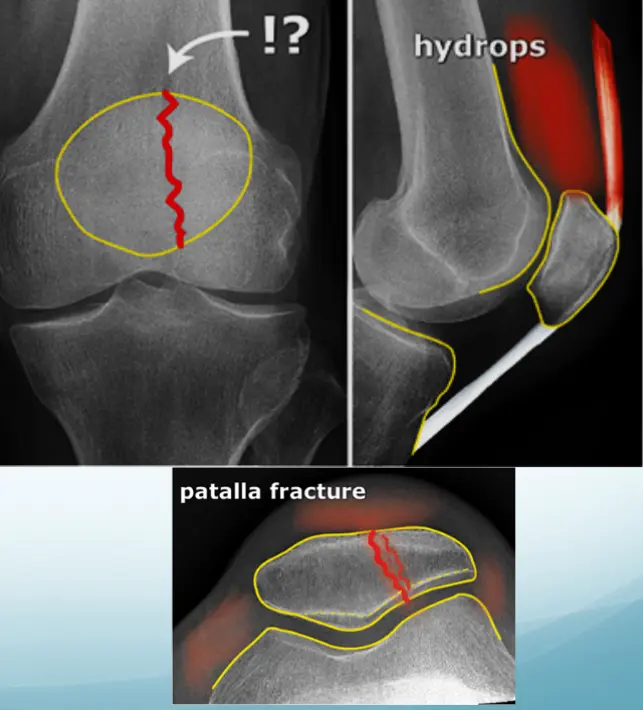

Bipartite Patella - Normal Variant

- No localized tenderness

- Superolateral

- Line not that of a fresh fracture